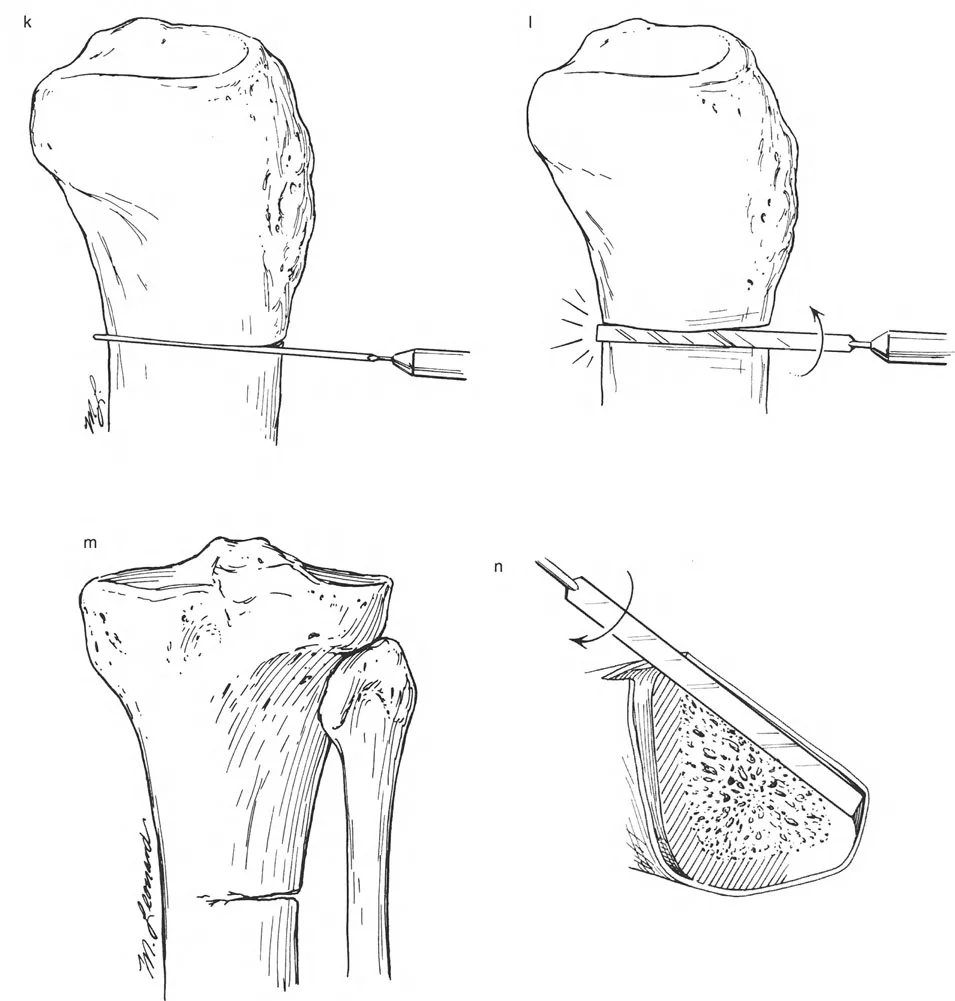

المفصلات القريبة من المفصل وقواعد قطع العظم (Osteotomy Rules)

عند التعامل مع التشوهات الواقعة بالقرب من خط المفصل - مثل التقوس الشديد في الجزء العلوي من الساق (مرض بلونت) أو التشوه الفحجي في الجزء السفلي من عظم الفخذ - يصبح وضع الجهاز مقيدًا هندسيًا. إن المتطلبات البيولوجية للحفاظ على كبسولة المفصل، وتجنب وضع الأسلاك داخل المفصل، ومنع التهاب المفاصل القيحي، غالبًا ما تجبر الجراح على وضع الحلقة المرجعية على مستوى مختلف تمامًا عن مركز دوران الانحراف (CORA) الفعلي.

تحدي مركز دوران الانحراف (CORA) القريب من المفصل

لمطابقة مفصلة المثبت الخارجي مع المستوى الدقيق لمركز دوران الانحراف (CORA)، يجب غالبًا بناء المفصلة فوق أو تحت مستوى الحلقة الفعلية. يُعرف هذا في مبادئ بالي باسم تجميع المفصلة القريبة من المفصل (juxta-articular hinge assembly).

إذا كان مركز دوران الانحراف (CORA) يقع بالقرب من خط المفصل، فإن وضع حلقة إليزاروف القياسية عند هذا المستوى بالضبط مستحيل دون انتهاك مساحة المفصل أو شد الهياكل الكبسولية الحيوية. لذلك، يتم تثبيت الحلقة المرجعية بالعظم الكثيف أو العظم الطويل المتاح، ويتم بناء آلية المفصلة باستخدام قضبان ملولبة، ولوحات توصيل، ودعامات. ثم يتم "إنزالها" (أو رفعها) لتتطابق تمامًا مع مركز دوران الانحراف (CORA) الهندسي الحقيقي.

قيود الأسلاك والدبابيس في القاعدة 2

لتحقيق هذه الترجمة الضرورية والمقصودة بسلاسة باستخدام إطار دائري كامل الأسلاك، يلزم استخدام أسلاك الزيتون المعاكسة (counter-opposed olive wires). تعمل أسلاك الزيتون كقوى سحب ديناميكية، تسحب قطعة العظم على طول الحلقة أثناء فتح المفصلات. بدون أسلاك الزيتون، سيبقى العظم ثابتًا بينما تتحرك الحلقة عبر الأنسجة الرخوة، مما يسبب نخرًا شديدًا في الجلد.

على العكس من ذلك، إذا تم استخدام دبابيس نصفية (مسامير شانز)، فإنها تقيد العظم بطبيعتها بالحلقة. نظرًا لأن الدبابيس النصفية هي أذرع صلبة (مثبتة من طرف واحد بالحلقة ومغروسة في العظم من الطرف الآخر)، فإنها لا تسمح للعظم بالانزلاق على طول محور السلك. هذا يجعل أسلاك الزيتون غير ضرورية للترجمة في منشآت الدبابيس النصفية، ولكنه يتطلب من الجراح التأكد من أن الدبابيس النصفية قوية بما يكفي (عادةً دبابيس بقطر 5 مم أو 6 مم مطلية بهيدروكسي أباتيت) لتحمل لحظات الانحناء الناتجة عن الترجمة.

نصائح جراحية للمنشآت القريبة من المفصل

| المبدأ | التطبيق السريري | تحذير / خطأ محتمل |

|---|---|---|

| التحقق من CORA | دائمًا تحقق من CORA الحقيقي في الأشعة السينية الطويلة للطرفين قبل بناء المفصلة. | الاعتماد على الأشعة السينية القصيرة للركبة سيؤدي إلى CORA غير دقيق وبالتالي سوء محاذاة. |

| ACA العمودي | تأكد من أن محور المفصلة (ACA) عمودي تمامًا على مستوى التشوه. | محور ACA مائل سيحدث تشوهًا ثانويًا غير مرغوب فيه (مثل تصحيح التقوس ولكن إحداث الانحناء الأمامي). |

| تخليص الأنسجة الرخوة | عند استخدام قاعدة قطع العظم 2، احسب الترجمة المتوقعة وتأكد من أن الأنسجة الرخوة يمكن أن تستوعبها. | عدم مراعاة الترجمة يمكن أن يتسبب في اصطدام العظم بالجلد، مما يؤدي إلى النخر. |

| تقابل الأسلاك | استخدم ما لا يقل عن سلكين زيتون متقابلين لكل قطعة إذا كنت تتجنب الدبابيس النصفية. | الأسلاك الزيتون الفردية ستسبب قصًا ودورانًا غير مرغوب فيه حول محور السلك. |